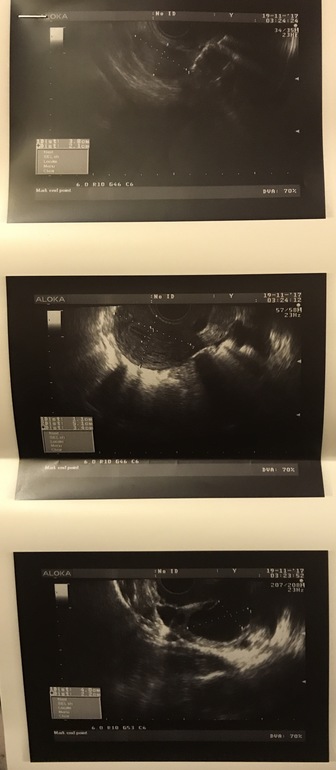

Не пойму девчонки а в чем отличие киста ЖТ от Ф кисты? И действительно нельзя пробовать зачатие чтобы киста не лопнула? Я думала наоборот нужно пробовать вдруг получится, а тут на форуме пишут что даже несколько месяцев может пройти чтобы она ушла. Ничего не понимаю((( может кто увидит на фото еще что-нибудь

Фолликул 3 мм на какой день цикла? Если ДФ в другом яичнике, не там, где киста, то все возможно. Много читала, что у девочек получается с кистами забеременеть. Просто смотрите на размер кисты и свои ощущения ( у меня при КЖТ тянуло живот с этой же стороны и как будто щёлкало что-то , размер был 43х35, соответственно при таких ощущениях я боялась заниматься сексом). Завтра 4ДЦ пойду на УЗИ, посмотрю, что с кистой. Но вряд ли уйдёт сразу 🙈

11 день цикла. Так вообще вот сразу после месячных тянуло один день и все щас тишина. Я бы и не поняла что киста какая-то если бы не узи. Просто давно на 11 день цикла были фоликулы 8 мм хотя бы а 3 мм совсем что-то мизер.

Фолликулярная киста образуется от того, что не произошло овуляции и фолликул перерос. И планировать в этом цикле нет смысла, так как яйцеклетка не вышла. А можно ли заниматься сексом, либо стоит чуть чуть повременить зависит от размера этой кисты. По идее к началу следующего цикла такая киста рассасывается. А киста желтого тела это значит произошла овуляция и желтое тело увеличено. А какие последствия и как долго она уходит я не в курсе.

А вы не знаете 4,0*2 см это как считается 4 см?

Думаю считается по самой большой длине. Я однажды стимулировалась и за 7 дней стимуляции вырастили 9 см фолликулярную кисту. Причём на УЗИ ходила каждые 2-3 дня. И на предыдущем УЗИ было все ок. Врач мне сказал что в его практике это первый случай. Не хочется конечно быть такой уникальной. Так что за кистами лучше следить. Они не всегда требуют лечения. Главное чтобы вам врач сказал нужно или нет лечить.